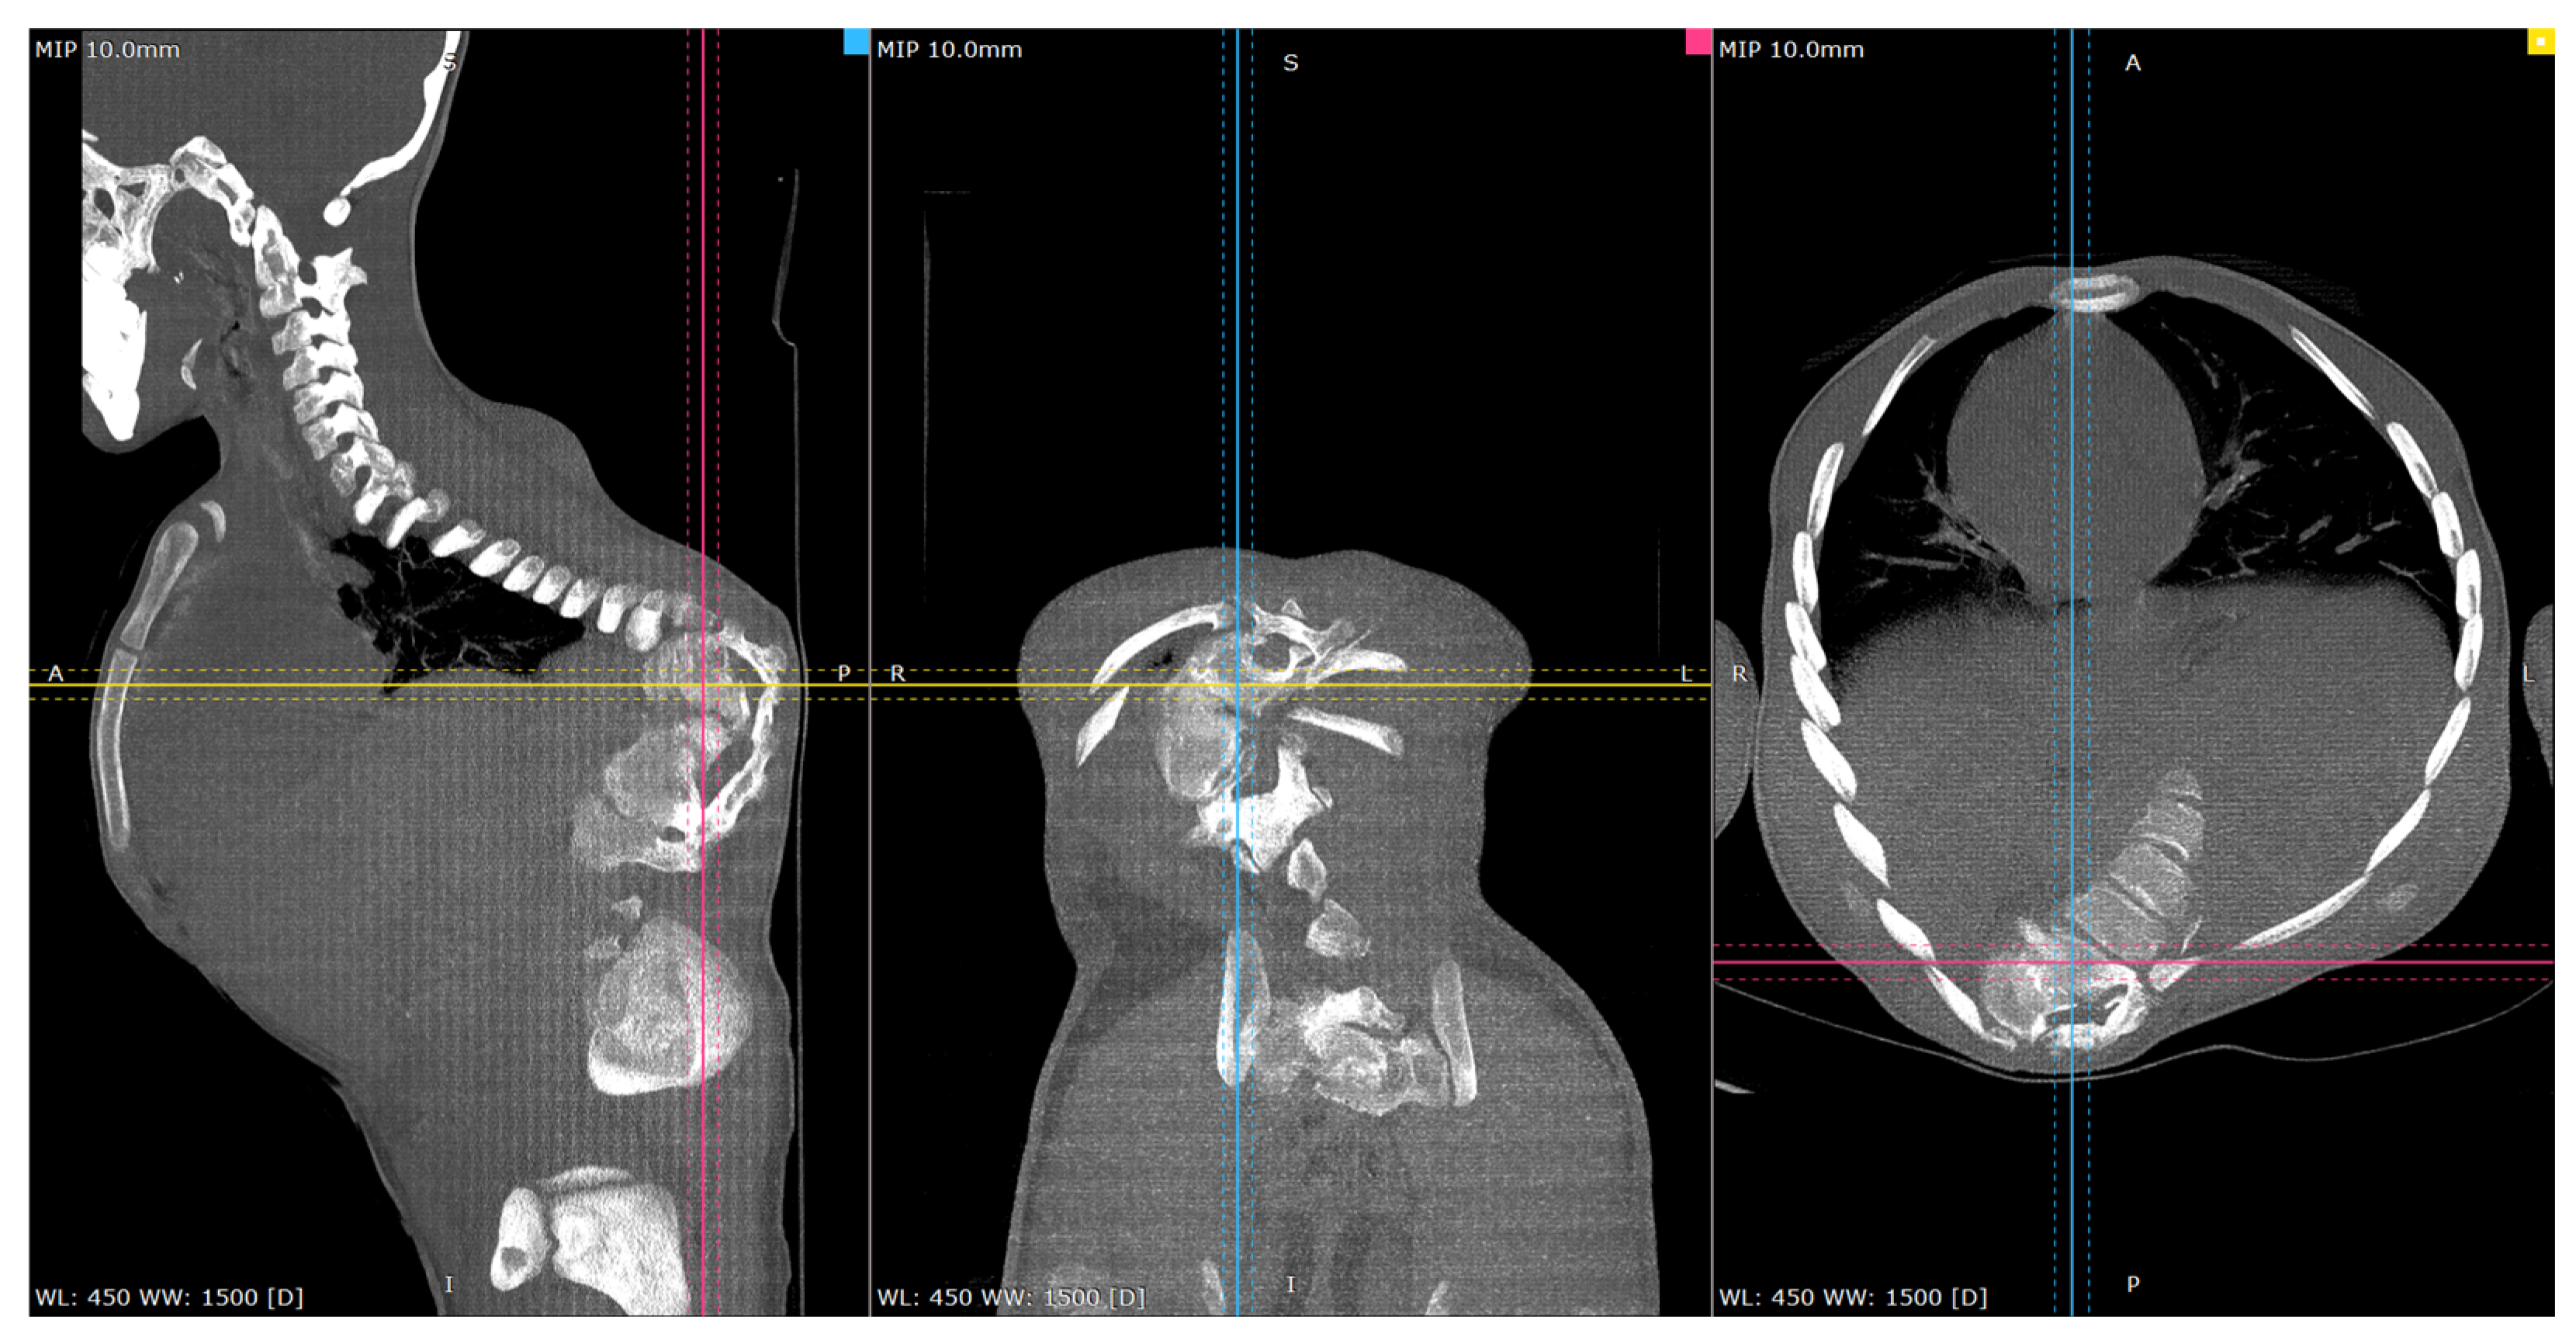

3.2. Diagnostic Assessment

Full-length standing scoliosis films demonstrated a congenital deformity at T12-L1; he was coronally shifted to the right and had a 100-degree thoracolumbar junctional kyphotic deformity. The severe congenital deformity was better characterized on CT images with hemivertebrae and incomplete formation of the posterior elements from T10 down through L2, most pronounced at the T12 vertebral level. The CT images were used for pre-operative planning for the computer-navigated robotic-assisted placement of pedicle screws from T5 down to L4 across his congenital anomalies (Figure 2, Figure 3, Figure 4 and Figure 5).

Figure 4.

Representative pre-op CT scan views of the congenital deformity. Cross-reference grid lines mark the intersection of the corresponding image planes: Blue—sagittal; Pink—Coronal; Yellow—Axial views.